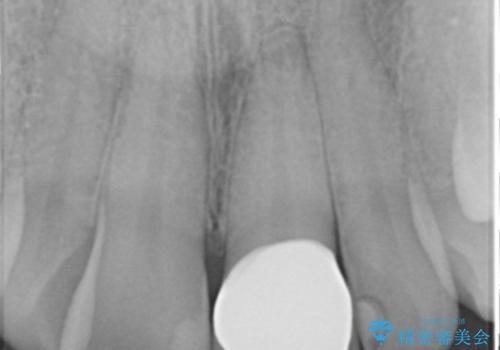

歯の欠損範囲が大きいことから、同様にレジン修復しても欠けやすいためセラミッククラウンによる補綴を行いました。

患者様のご希望により、最終補綴前にホワイトニングを行いました。

天然歯と見紛うほどの自然な仕上がりに喜んで頂けました。

クラウンの繊細なグラデーションや自然な表面性状・形態は熟練した技工士さんの技術の賜物です。

被せ物の種類:ジルコニアオールセラミッククラウン スペシャル